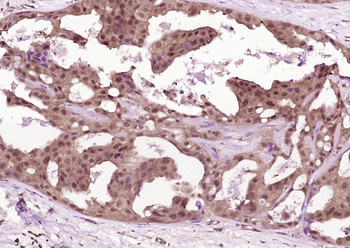

IL-1R2 Rabbit Polyclonal Antibody

FC, IF, IHC-Fr, IHC-P, WB

KLH conjugated synthetic peptide derived from human IL-1R II (301-398/398aa)

应用稀释比例:WB=1:500-2000, IHC-P=1:100-500, IHC-F=1:100-500, IF=1:100-500, Flow-Cyt=1μg/test